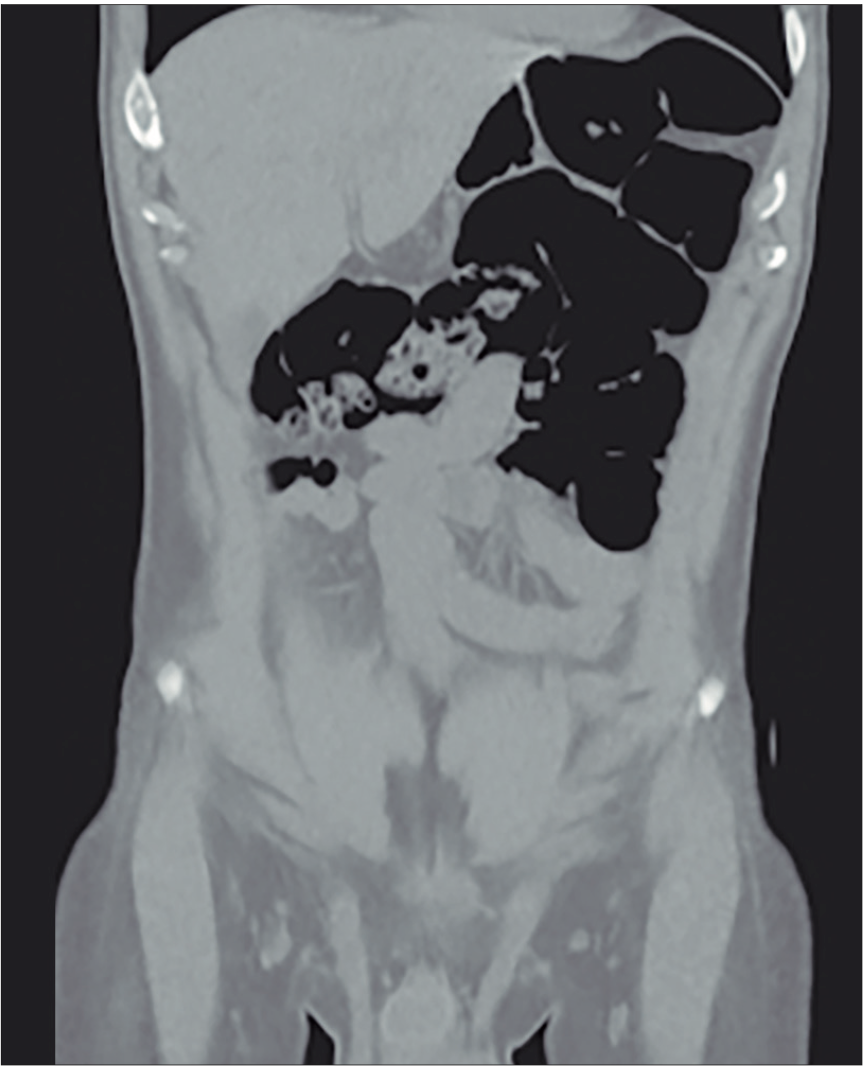

Posteriormente se realiza una tomografía computarizada de abdomen y pelvis sin contraste donde se observan asas intestinales dilatadas (Figura 1), ciego levemente distendido con abundante contenido propio, que cruza la línea media hacia el flanco izquierdo (Figuras 2 y 3), tracción e ingurgitación de los vasos mesentéricos (Figura 4).

Figura 1. Asas colónicas dilatadas